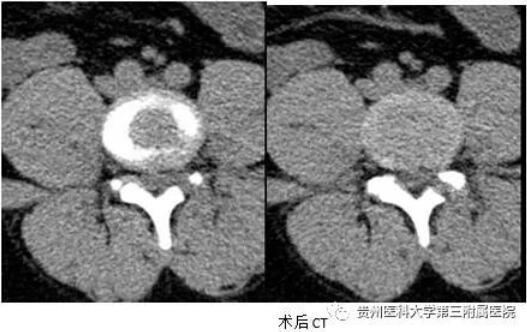

经过充分地沟通和术前准备,近日,我院骨科副主任、主任医师熊永发带领科室团队,在局部麻醉下,为寒先生实施了椎间孔镜手术治疗。手术过程十分顺利,仅1个切口,出血约10毫升。

术后,寒某行走自如,折磨他的腿疼也消失了。他非常开心并感叹:“一年多没有正常走路了,能正常行走的感觉太好了!”